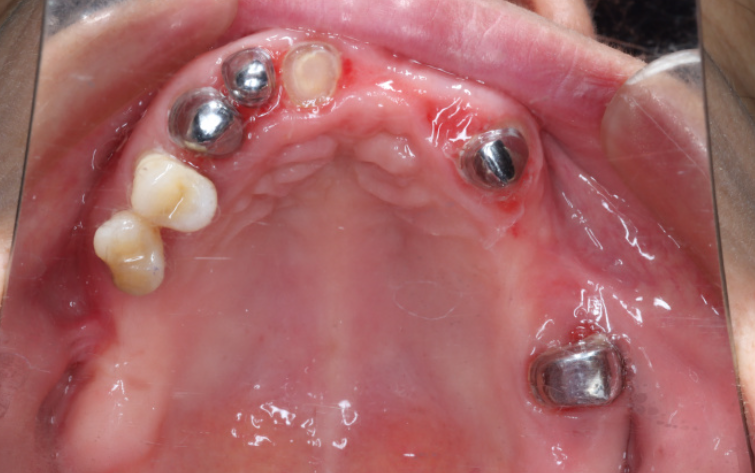

2. 牙周病患者:对于基牙条件较差但仍有保留价值的患者,尤其是牙周炎导致牙齿松动经治疗后需要修复的情况,套筒冠义齿是一个合适的选择。它可以通过形成牙周夹板作用,固定松动牙。

4. 牙齿松动明显:二度至三度松动的牙齿,通过套筒冠形成牙周夹板作用,将松动牙固定在一起,形成一个整体,增强牙齿的稳定性。

5. 牙周夹板作用:对松动牙齿起固定作用,形成整体结构互相扶持,可保留二度至三度松动的牙齿,避免牙齿过早脱落。